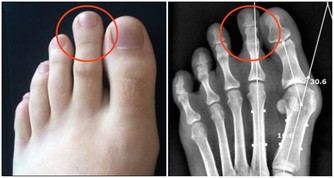

牙垢也叫牙菌斑,是附著在牙齦冠部、頸部及牙縫間的污垢。

牙垢主要是食物殘渣、口腔黏膜脫落的上皮、唾液及細菌混合而成。

牙垢久積,容易鈣化成牙結石。